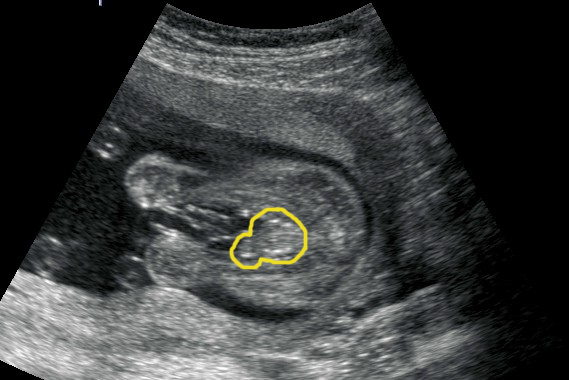

Can anyone help? Any techs that can help would be so much appreciated. The photo is at 19 weeks where i was told boy, then today the doc told me looked like a girl to her although bub wasnt in the greatest position she said she couldnt see anything that looked like boy bits. So confused now. Could this possibly be a girl???